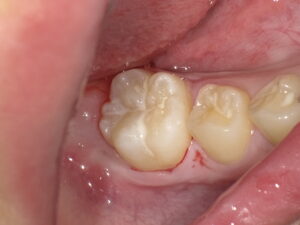

自費専用のコンポジットレジンを充填します。その際にもともとの歯の形、溝、色調を再現します。(ここが1番時間がかかるところですし、こだわりポイントです)

治療痕が目立たない、自然で長持ちする治療です。

- 見た目が自然な材料(白くてきれい):複数の色を使い分け、天然歯のような透明感を再現できます。